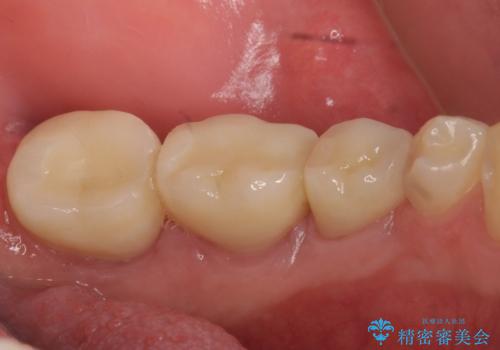

手術後歯茎の治癒を待ち、オールセラミッククラウンによる補綴を行いました。

今回用いたオールセラミッククラウンはジルコニアフレームという白い素材の上にセラミックを盛っているため、審美性が非常に高いのが特徴です。

また、ジルコニアは人工ダイヤモンドの材料にも使われているほど高い強度を持っており、そのためオールセラミッククラウンは審美性だけでなく、奥歯やブリッジの補綴も可能とするクラウンです。